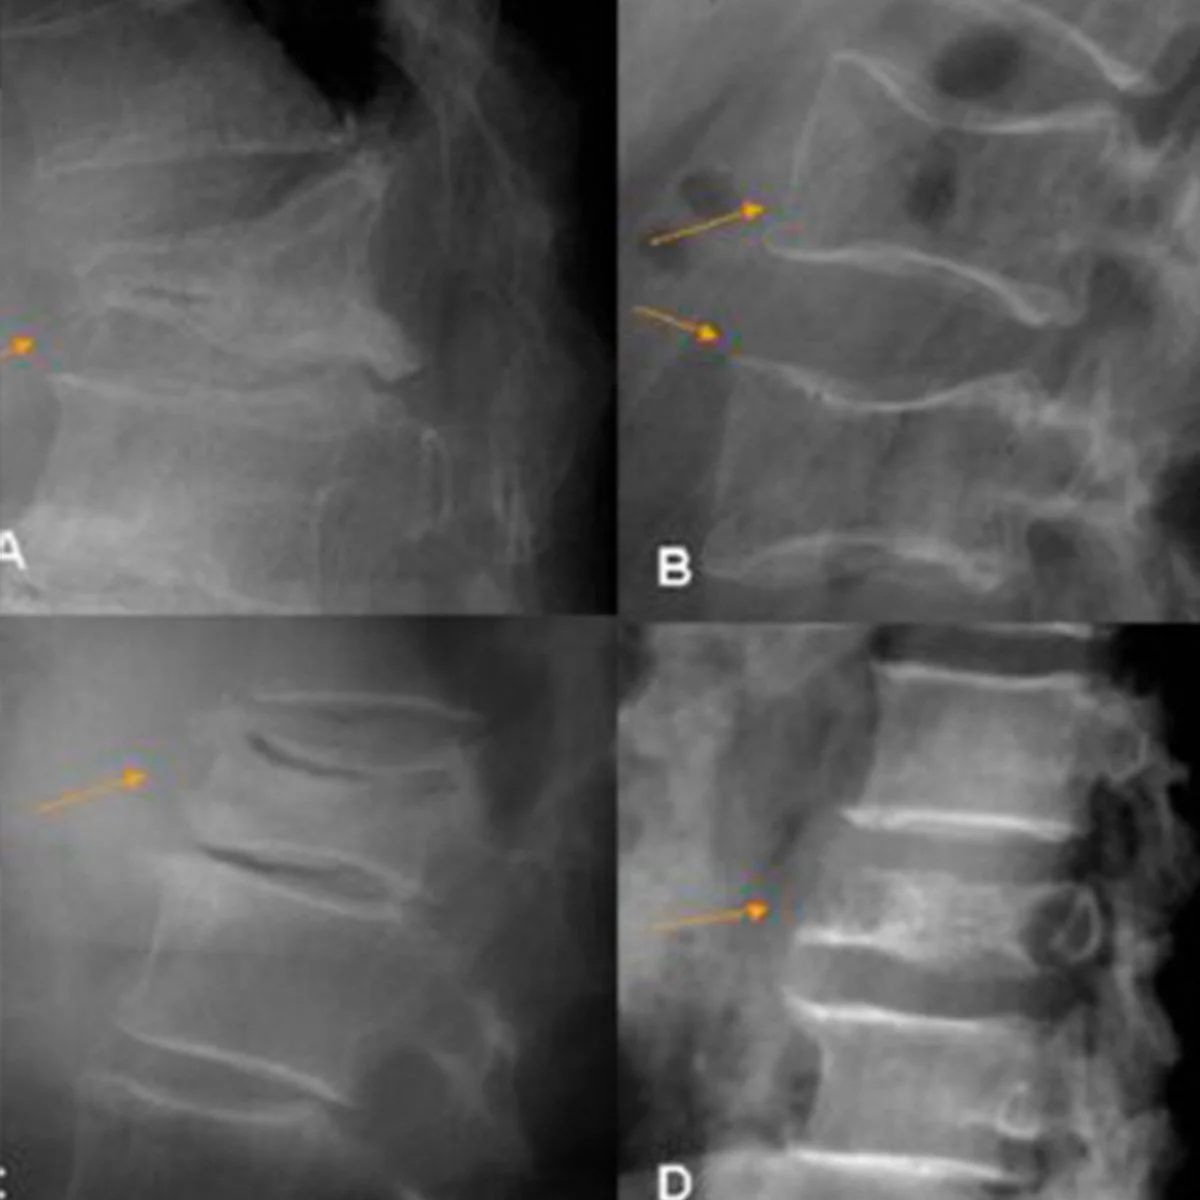

Espondilolistesis

Es una afección en la que una vértebra se desliza hacia adelante sobre la vértebra inferior, generalmente en la región lumbar.

Fracturas de columna

Es una lesión grave en la que uno o más huesos de la columna vertebral se rompen, generalmente por caídas, accidentes, osteoporosis o traumatismos incluso de baja energía.